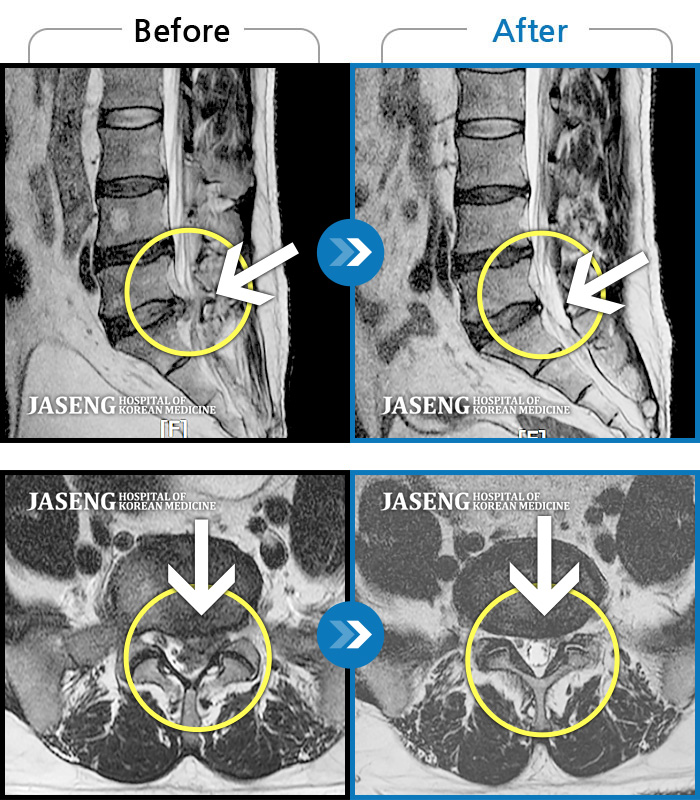

허리디스크

도움받은 사례

인천 · 조남훈 원장

재채기 하고 나서 다리에 힘이 안들어가요.

촬영시기

2021.11.10 ~ 2024.11.26

2024.12.04

조회수 443